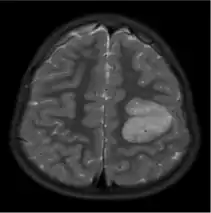

MRI scan of a four-year-old boy with AG. The light grey part indicated a hyperintense and elastic lesion in his left posterior frontal lobe.[12]

The neurological features of AG tumors are visible via CT scanning or MRI. A clear indication of AG may appear as well-delineated, solid, T2-hyperintense, non-enhancing cortical lesions located in the temporal or frontal lobes in MRI.[1] Another diagnostic trait is a stalk-like extension to adjacent brain ventricles.[13] These traits are similar to low-grade gliomas from a radiological perspective.

The results from CT scanning and MRI are different in terms of clarity and effectiveness of diagnosis. AG displays an expansive non-enhancing cortical tumor in CT scanning, whereas MRI shows a relatively clearer appearance of AG and the tumors appear to be infiltrative, well-defined, and hypointense with T1 lesion.[4] T2/FLAIR lesions indicate AG as a tumor tissue with some extension toward the ventricles along vessels.[4] The possibility of cystic-appearing areas exists as well. In some cases, MRI results show an increase in ribbon-like signal on T1W1 lesions.[4] The clear radiographic outcomes of MRI makes it the more widely used option in the diagnosis of AG.[4]

Nevertheless, precise diagnosis of AG from other phenotypically similar gliomas (such as astroblastoma or ganglioglioma) is a challenge merely based on MRI or CT scanning.[14] The main difference between AG and ganglioglioma could be only AG shows enhancement over time. Compared to AG, astroblastoma often has a discrete border in epithelioid cells and shows vascular sclerosis symptoms.[15]